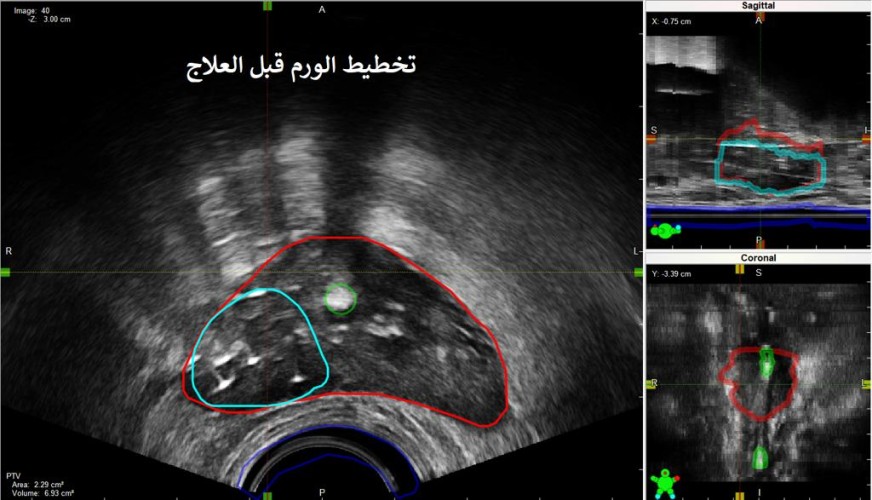

تمكن فريق طبي من مركز الأورام الشامل في مدينة الملك فهد الطبية إحدى مكونات تجمع الرياض الصحي الثاني من علاج ورم في غدة البروستات، بواسطة العلاج الموضعي الجزئي (براكي ثيربي) باستخدام أجهزة متقدمة موجهة بالأشعة الصوتية لمريض في العقد السابع من عمره.

وأوضح رئيس الفريق الدكتور سعد الرشيدي؛ أن المريض تلقى 39 جلسة من العلاج الإشعاعي الخارجي قبل 5 سنوات بعد تشخيصه بسرطان البروستات الموضعي.

وأضاف أنه منذ عام تبين بعد المتابعة عن طريق فحوصات الدم والأشعة المقطعية والنووية الصبغية وجود ورم رجعي موضعي بحجم 2 سم داخل البروستات؛ وبعد مناقشة الخيارات العلاجية تقرر استخدام العلاج الموضعي “براكي ثيربي” الجزئي .

وأبان د. الرشيدي ؛ أن استحداث العلاج الموضعي “براكي ثيرابي ” الجزئي يعتبر الخيار الأنسب لمحدودية المضاعفات ونسبة الشفاء التي تتجاوز 70% و هذا ما تم استخدامه لهذا المريض.

وفي تفاصيل الإجراء قال د. الرشيدي: “بعد التخدير الموضعي يتم زرع الإبر الجراحية داخل الورم باستخدام أجهزة متقدمة موجهة بالأشعة الصوتية ومن ثم إيصال الجرعة العلاجية الكافية للتخلص من الورم؛ وبإمكان المريض الخروج من المستشفى بنفس اليوم”.